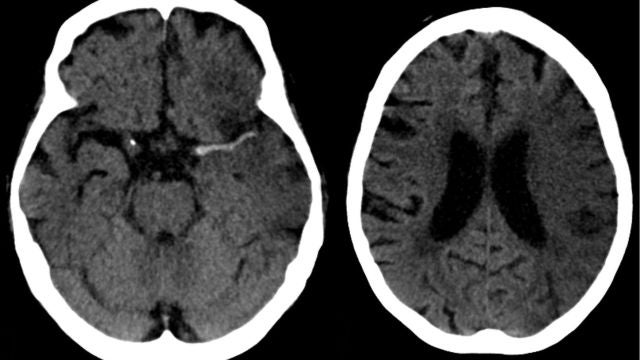

Ictus en arteria cerebral media (izda) y evolución a las 7 horas (dcha). wikipedia